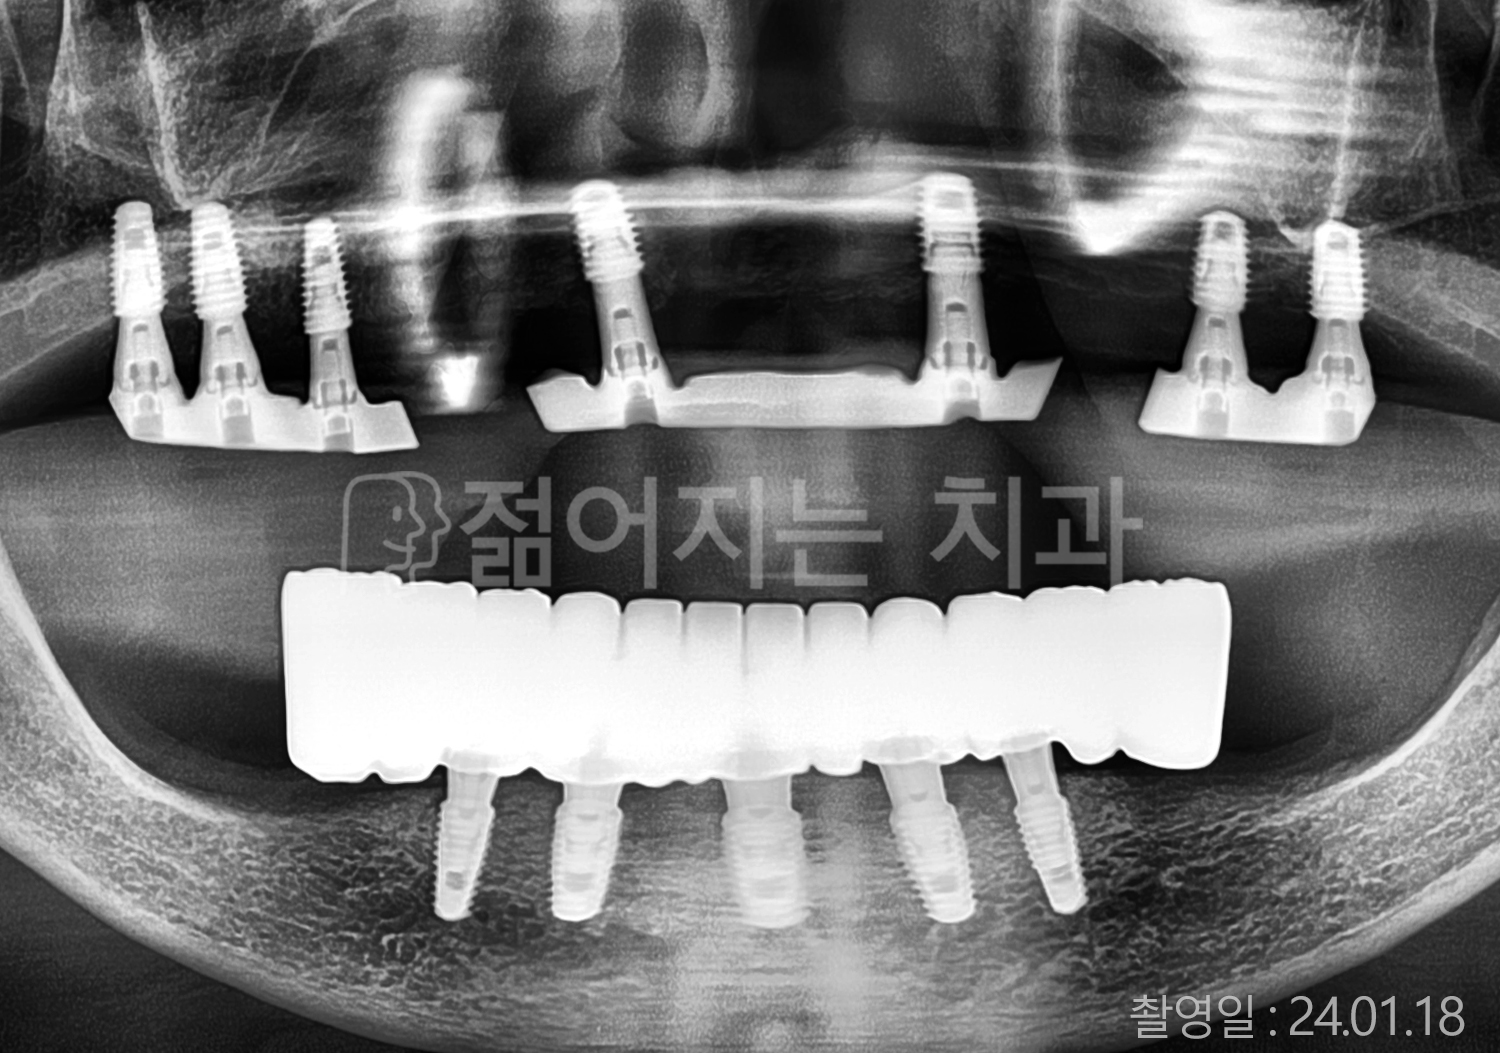

• 50대 고혈압, 당뇨, 고지혈증 전체치아 10개 이상 임플란트

• 60대 골다골증, 간경화 전체치아 10개 이상 임플란트

• 60대 고혈압, 고지혈증 전체치아 10개 이상 임플란트

• 50대 고혈압, 당뇨 전체치아 10개 이상 임플란트

• 60대 고혈압 전체치아 10개 이상 임플란트

• 60대 전체치아 10개 이상 임플란트

• 60대 고지혈증 전체치아 10개 이상 임플란트

• 40대 전체치아 10개 이상 임플란트

• 70대 전체치아 10개 이상 임플란트